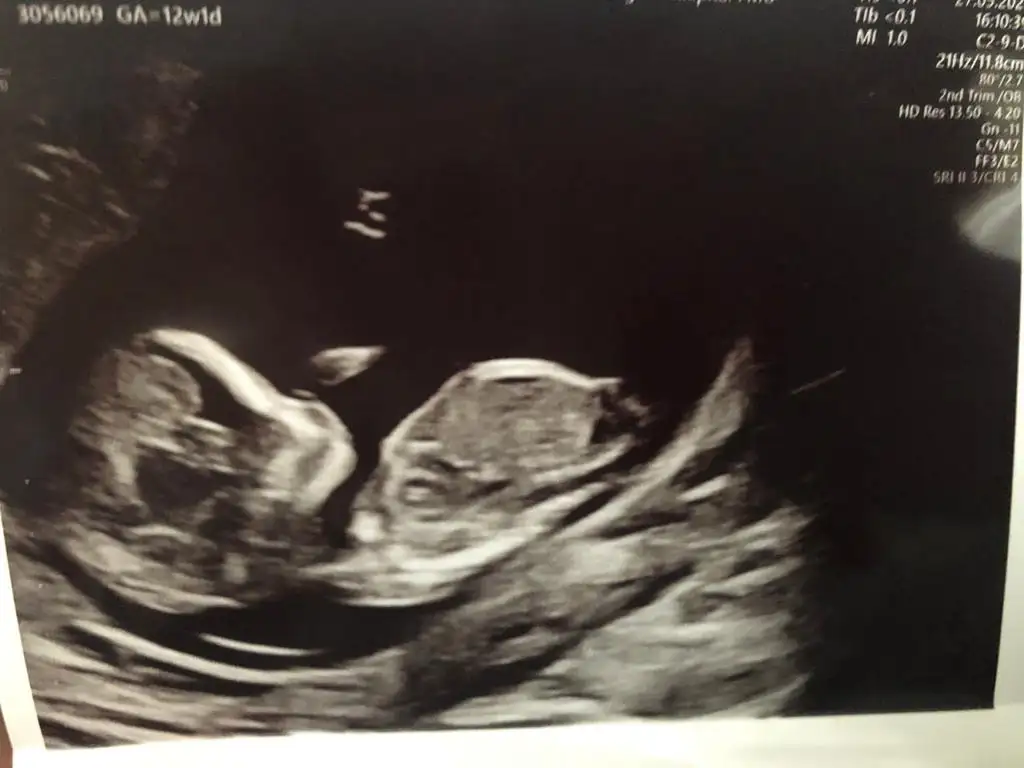

Rica etsem banada tahmin yaparmisiniz 8 haftada kiz demistiniz tekrar gondermemi istemistiniz dayanamadim bu usg 11 haftalik

Kız gibi net de değil kız sanki 12-13 olunca tekrar usg paylaşın